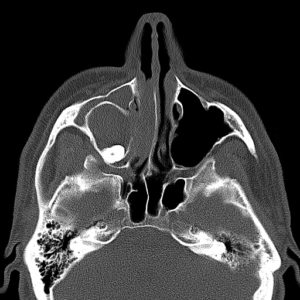

Ekstrakcja, czyli inaczej usuwanie zębów, to jeden z podstawowych zabiegów w zakresie chirurgii stomatologicznej. Wykonywany jest w znieczuleniu miejscowym – prawidłowo podane uwalnia od bólu w stu procentach. Od każdej reguły zdarzają się jednak wyjątki. Oto właśnie taki. Prawa górna ósemka znajduje się pod dnem oczodołu, w świetle zatoki szczękowej (przy okazji zacienienie widoczne na zdjęciach może świadczyć o jej przewlekłym zapaleniu). W takim przypadku o „miejscówce” w ogóle nie było mowy. Żaden chirurg nie zgodziłby się na usunięcie tej ósemki w znieczuleniu miejscowym. Pacjent został przyjęty na Oddział Chirurgii Szczękowo-Twarzowej Uniwersyteckiego Szpitala Klinicznego w Opolu i tam, w warunkach bloku operacyjnego, został zoperowany w znieczuleniu ogólnym.